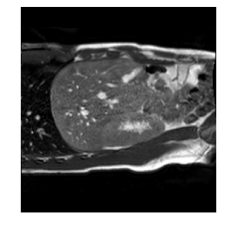

With this motivation, [6] proposed a convolutional neural network (CNN) based approach for temporal interpolation of navigators. Their CNN takes as inputs a fixed number of acquired images and learns to predict the missing images directly in the intensity space. This approach, which we call the Simple Convolutional Interpolation Network (SCIN), is a ’black-box’ formulation that does not incorporate any prior information about the interpolation process. Image prediction is guided only by the cost function used to optimize the network parameters. The issue with this is that it is unclear whether the image similarity measures that are generally used as cost functions suffice to ensure fidelity of the generated images to the original images. Indeed, Fig. 1b shows a case where an image interpolated using SCIN is quite blurry and misses several liver and lung structures present in the original image.

(a)                                (b)                                (c)

Figure 1: (a) Ground truth and (b,c) interpolated images from (b) baseline (SCIN) and (c) proposed method (MFIN). The image interpolated via SCIN is heavily blurred and misses several lung and liver structures, while the proposed method is able to preserve the details in the ground truth image.